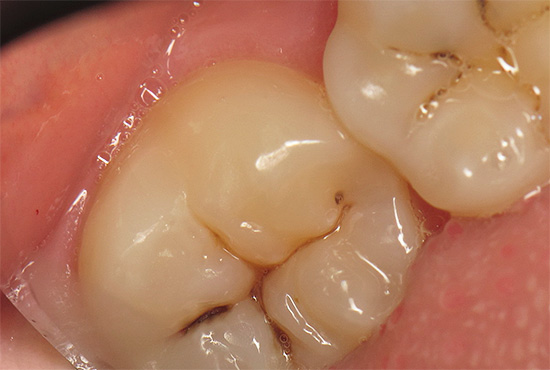

La foto sotto mostra un dente in cui sono visibili profonde cavità cariate interne sotto una luce intensa: